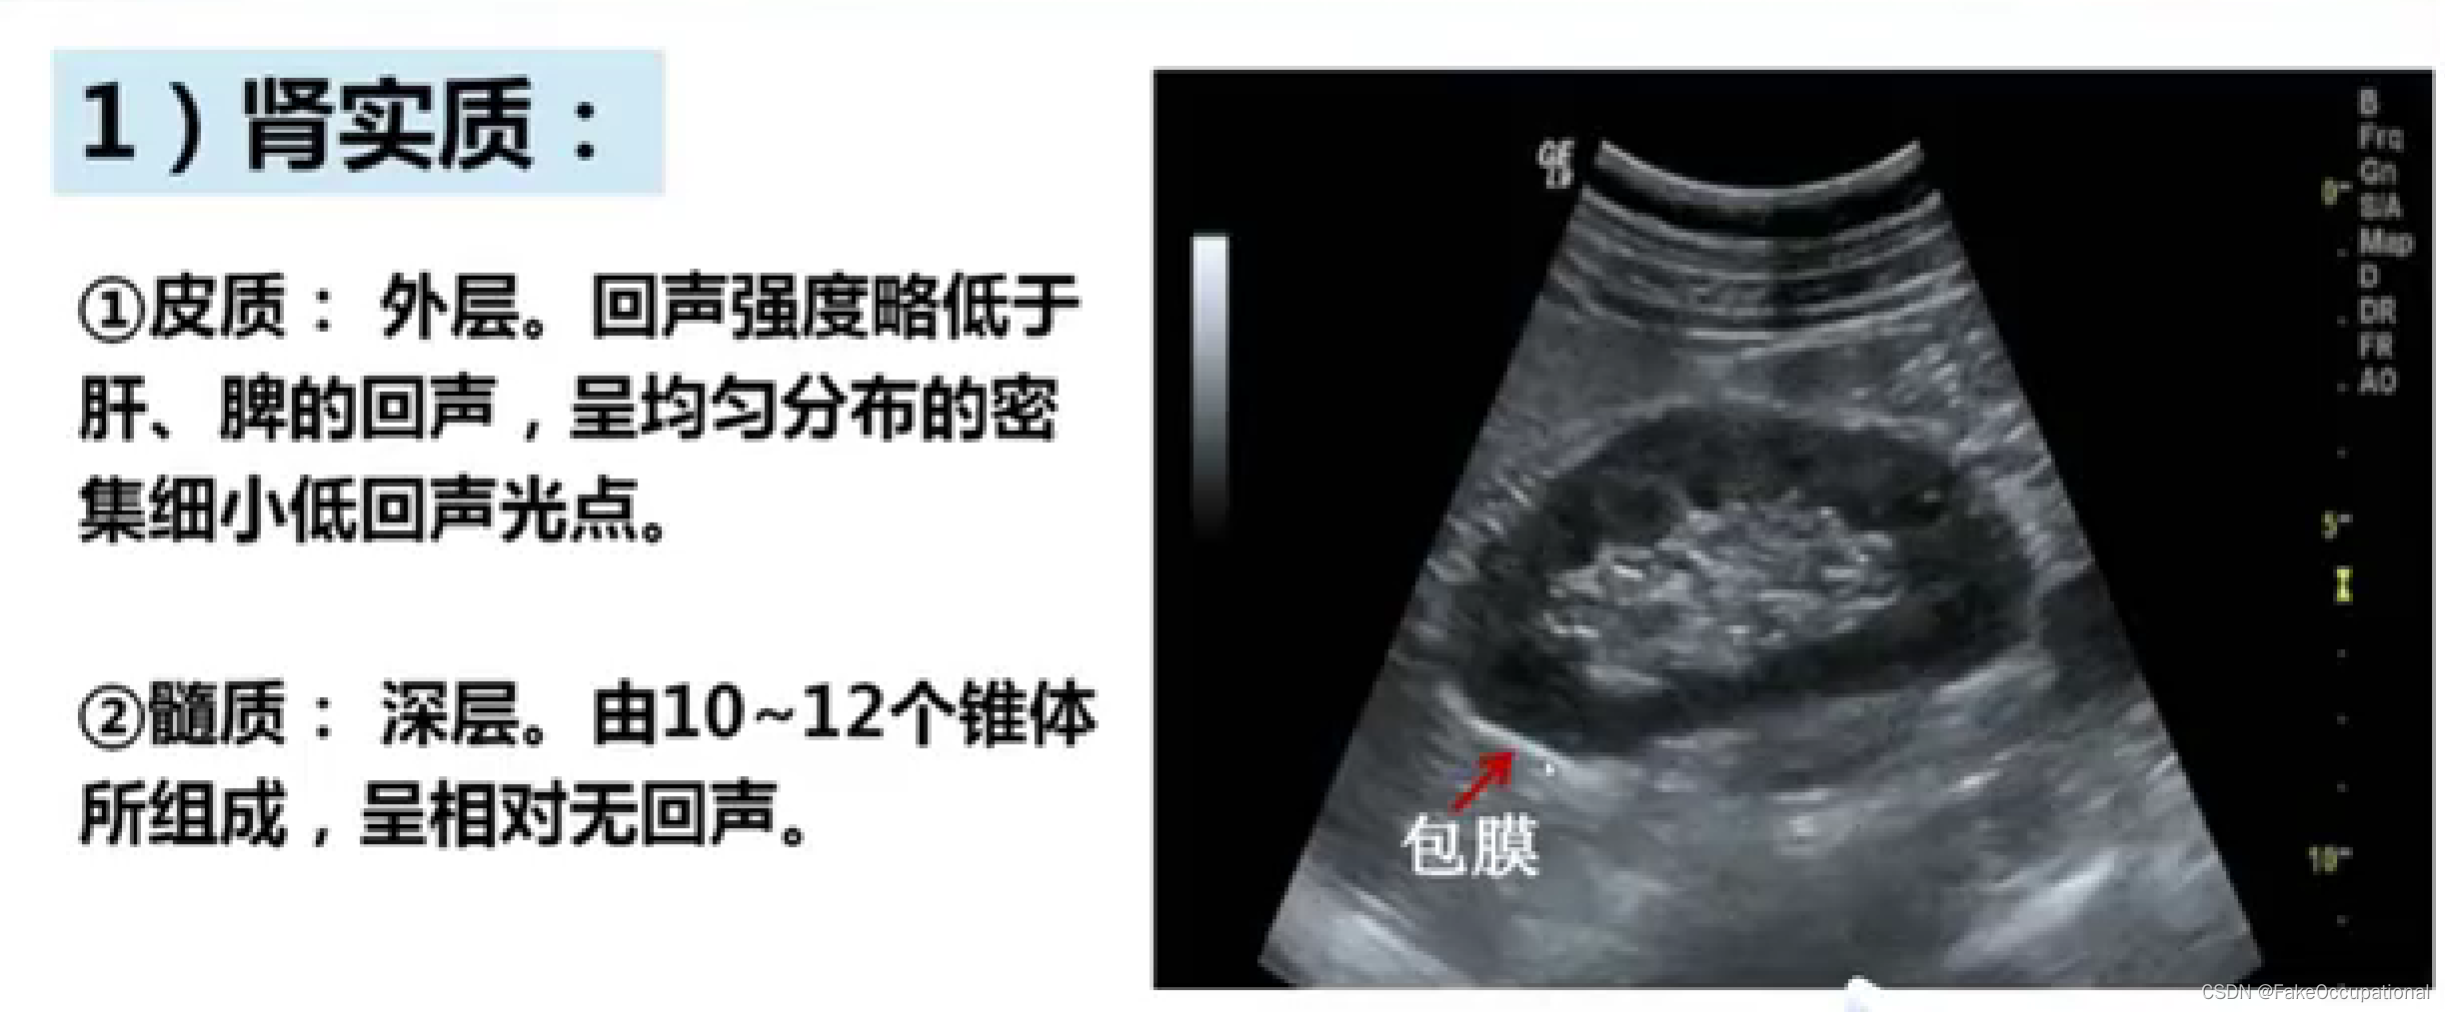

正常肾脏及肾血管超声表现